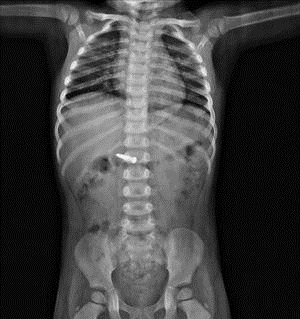

通常,医院通过X线检查来判断患者体内有没有异物,根据X检查把异物分为可显影异物和不可显影异物。

可显影异物:指在X检查中可以显示的异物,一般是一些密度较大的物品,比如:小铁丝、带金属的纽扣、硬币等等。